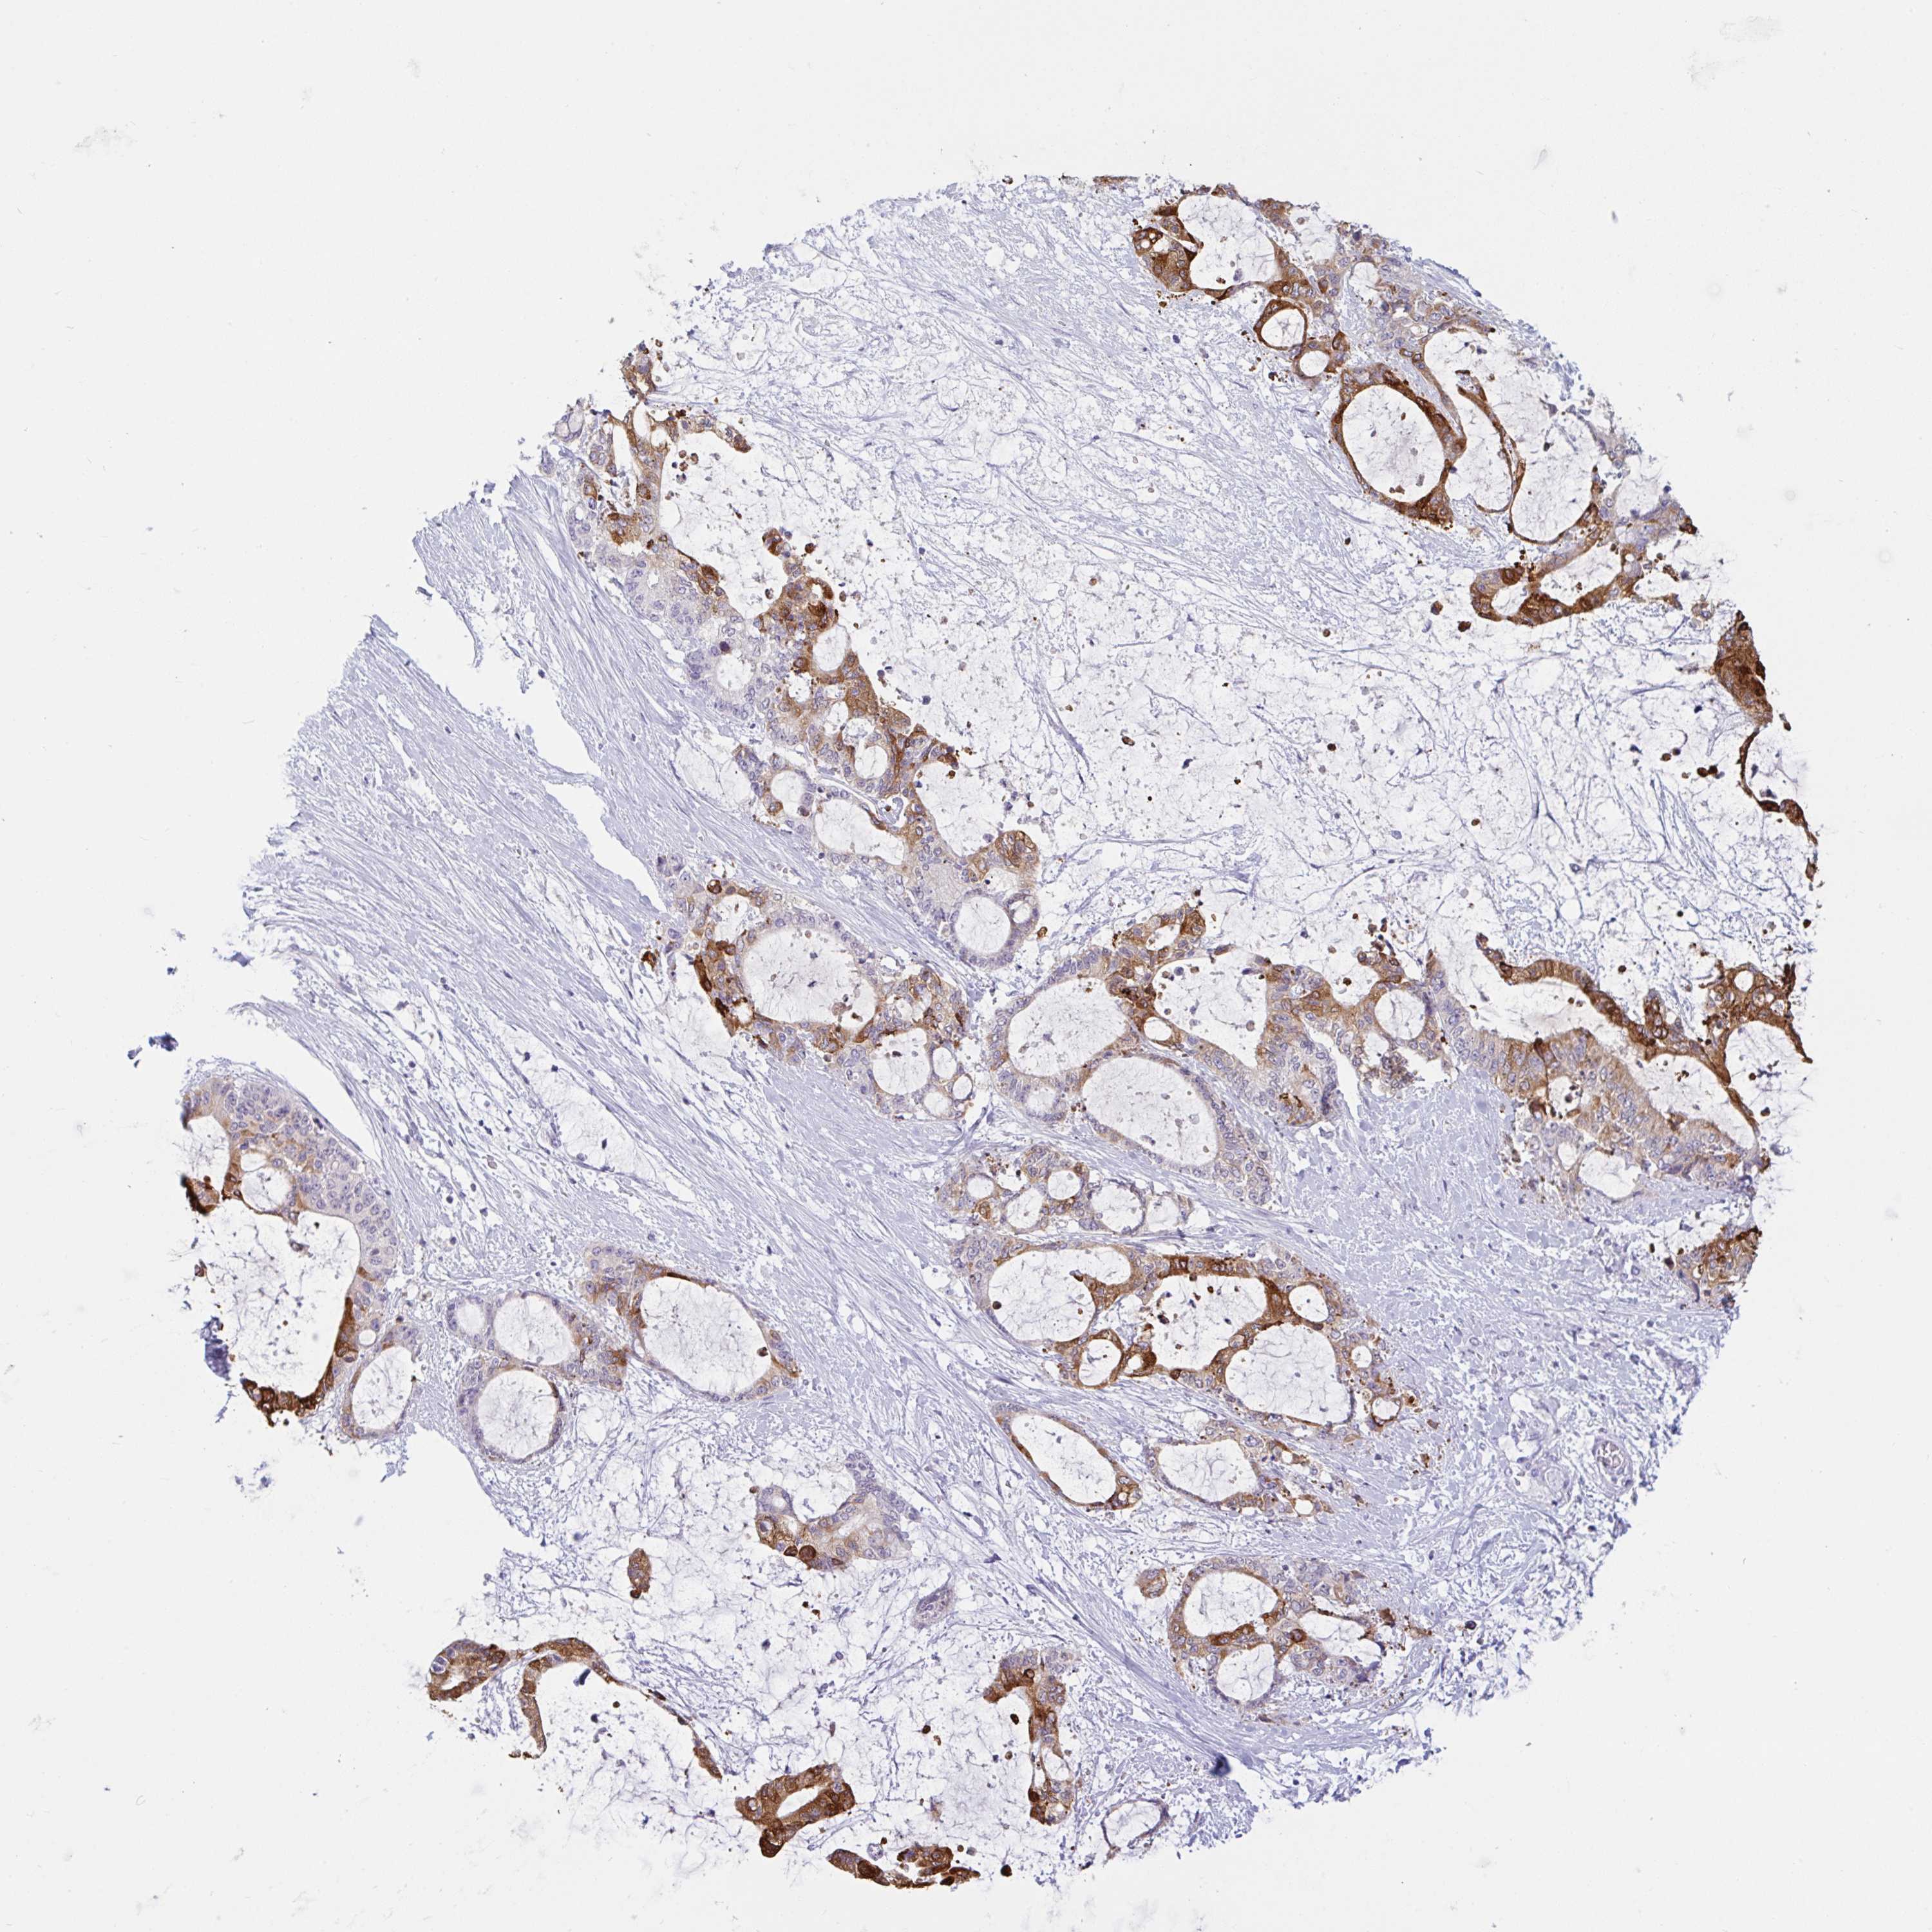

LIVER CANCER - Protein expressioni

A mouse-over function shows sample information and annotation data. Click on an image to view it in a full screen mode. Samples can be filtered based on level of antibody staining by selecting one or several of the following categories: high, medium, low and not detected. The assay and annotation is described here.

Note that samples used for immunohistochemistry by the Human Protein Atlas do not correspond to samples in the TCGA dataset.

Antibody stainingi

Antibody staining in the annotated cell types in the current human tissue is reported as not detected, low, medium, or high, based on conventional immunohistochemistry profiling in selected tissues. This score is based on the combination of the staining intensity and fraction of stained cells.

Each image is clickable and will lead to virtual microscopy that enables deeper exploration of all samples and also displays staining intensity scores, fraction scores and subcellular localization as well as patient and tissue information for each sample.

Antibody HPA012940

Antibody CAB032687